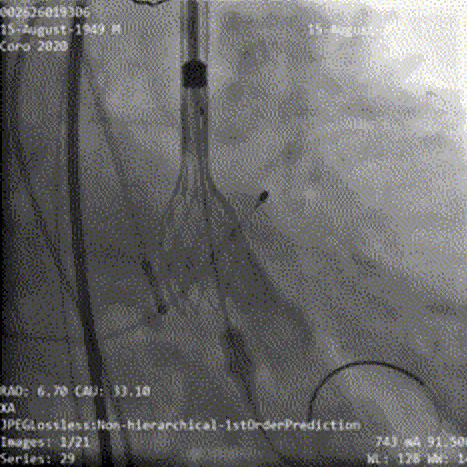

患者弓部较锐利、横位心,TaurusElite输送系统在snare辅助下完成过弓跨瓣后,AV29瓣膜于瓣环平面0mm开始定位释放;

Snare辅助下过弓、跨瓣

瓣膜初始定位